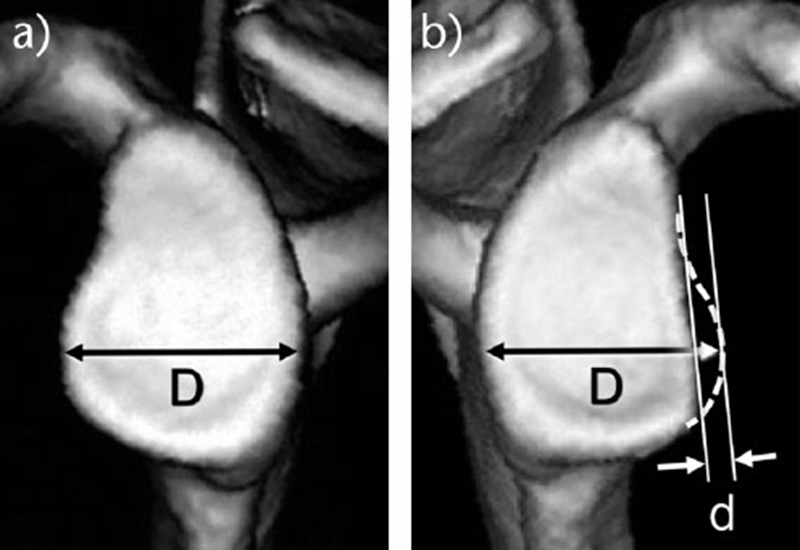

线形测量:a)对侧关节盂,完好无损。D代表完整的肩胛盂的宽度;

b)患侧的肩胛盂骨质缺损。D来自完整侧,完整的肾盂宽度D与缺损的肾盂宽度之间的差值为缺损宽度d。缺陷的大小表示为d/D×100(%)。